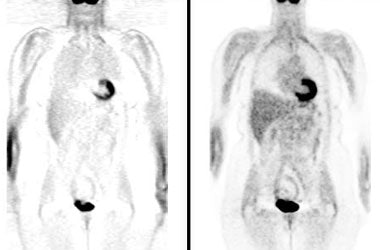

BGO versus LSO detector: The images below were acquired in 2D mode with a scan time of 5 min/bed emission and 3 min/bed transmission. The upper row of images were acquired on a BGO camera system and the lower row of images were acquired on a ECAT Accel LSO PET camera system. The data was reconstructed using normalized attenuation weighted OS-EM reconstruction. Image courtesy of Northern California PET Imaging Center, Sactamento, CA and CTI, The Power Behind PET. |